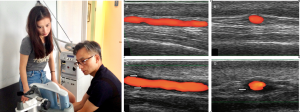

依據靜脈曲張治療指引,全程使用非侵入式設備,進行 靜脈曲張 的醫學性診斷。

利用『近紅外光』以非侵入式的方法對淺層靜脈曲張進行診斷,並可精準得知靜脈曲張之範圍與位置。

其原理是,曲張的血管,管徑會擴大,因此離表皮更近,而靜脈血液中含氧量較低的血紅素會吸收近紅外線,因此就會呈現血管顏色、形狀與位置。

靜脈血液的回流是靠血管周圍的肌肉收縮來完成的,瓣膜的功能就是要防止血液逆流,一但瓣膜功能有問題,表示位於深層的隱靜脈可能有問題。

透過超音波影像確定靜脈曲張的嚴重程度,滯留的血液在超音波影像上被偵測到,血管也會因為滯留血液的壓迫而變得粗大彎曲。